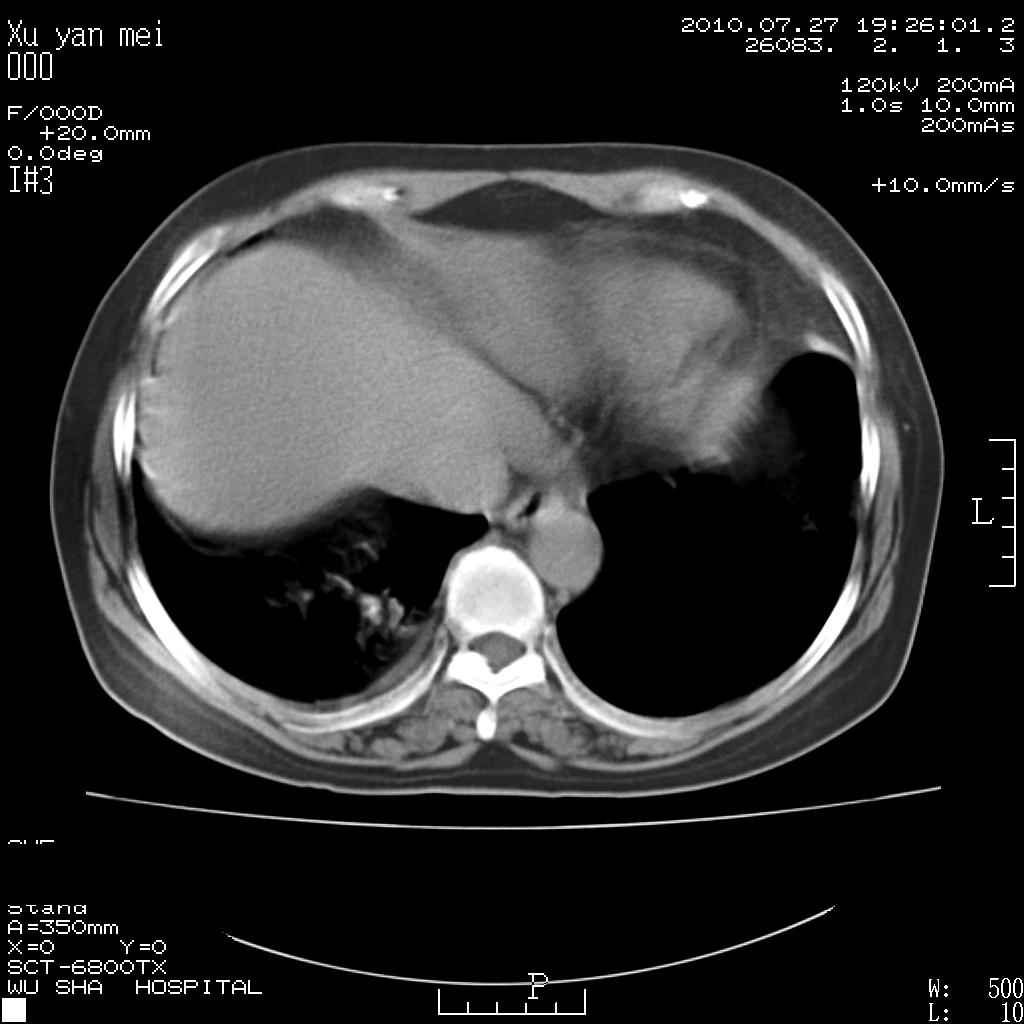

女,60岁,胸痛就诊,右肺结核?炎症?其它?(胸片右侧中上肺野确实看不到什么啊)

1)考虑两肺感染性病变;建议抗炎治疗后复查。2)双侧少量胸腔积液。

1)考虑两肺感染性病变;建议抗炎治疗后复查。2)右侧少量胸腔积液。

双肺炎症可能性大,建议抗炎后复查。右侧胸腔少量积液。双侧胸膜轻度增厚。